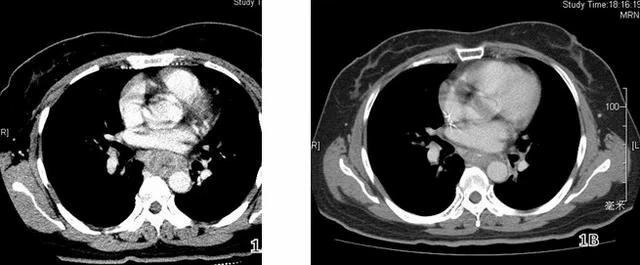

不去还好,一去吓破胆。经过病理抽血化验,食管CT扫描检查,医生初步判断陈栋有可能患上了食管癌晚期,但是还需要做进一步的组织病理检查。怎么可能,陈栋死都不信医生的话,拿着病理单和检查报告单,又跑了另一家大医院。结果还是一样。这下陈栋绝望了。